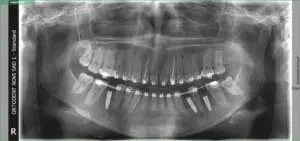

Rendgen snimak nakon ugradnje implantata

Na mestima gde su zubi nedostajali izvršeno je popunjavanje prostora implantima – precizno postavljenim titanskim šrafovima koji zamenjuju koren zuba.

Proces srastanja implantata sa kosti trajao je nekoliko meseci i pažljivo je praćen kontrolama i rendgenskim snimcima.